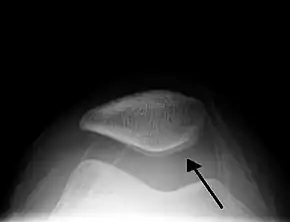

Joint effusion

A traumatic right knee effusion. Note the swelling lateral to the kneecap as marked by the arrow.